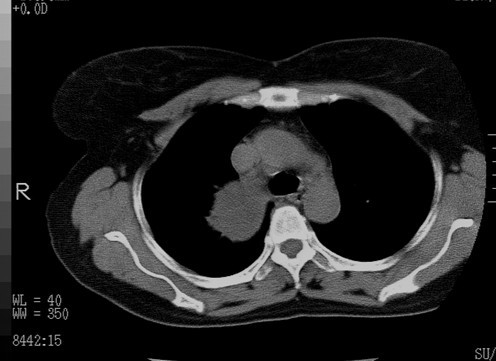

以下是引用随光逐影在2010-3-1 8:36:00的发言:[br]右上纵隔囊性占位性病变,考虑支气管囊肿,不排除神经源性肿瘤。